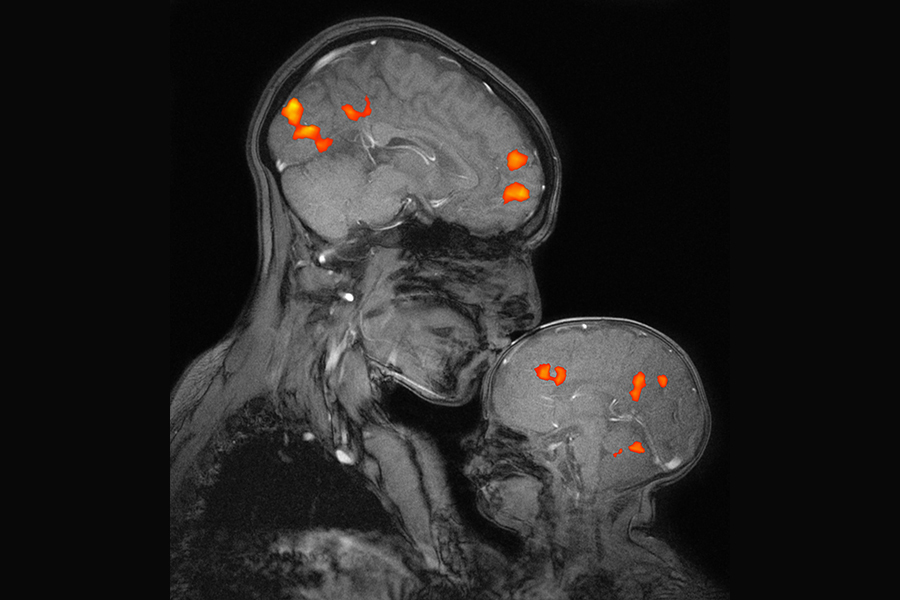

Čože sa im to aktivovalo? Pamäť, srdce a vízie?

Obrázok, zdroj: MIT. Funkcie mozgu, zdroj: AI: 🧠 Mozgové kortexy podľa funkcie: pamäť, emócie, vnímanie 1. Prefrontálny kortex (čelový lalok) Funkcia: rozhodovanie, pracovná pamäť, plánovanie, [...] Read more